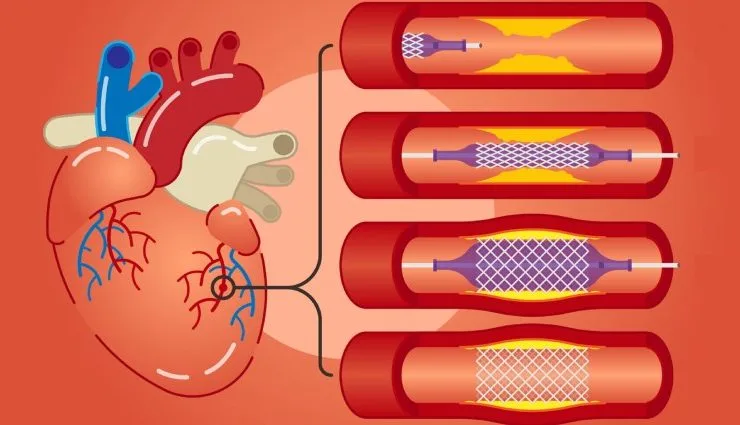

- آنژیوپلاستی کرونری

- آنژیوگرافی کرونری

- اهمیت مصرف دارو بعد از آنژیوگرافی و یا به اصطلاح فنر یا بالون زدن

- IVL ( لیتوتریپسی داخل عروقی)